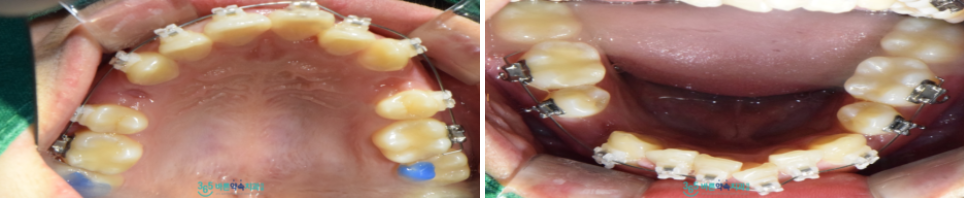

먼저 일부 충치 있는 치아들이 있어

치료를 먼저 진행한 뒤

망원동치아교정을 위해

위아래 작은 어금니를 하나씩 발치하였으며,

치아 배열을 위한

브라켓을 체결하였습니다.

브라켓 체결 후

정기적인 체크를 통해

치아의 이동을 확인하였으며,

눈에 띄게 배열이 가지런해지고 있는 것을

확인할 수 있었습니다.